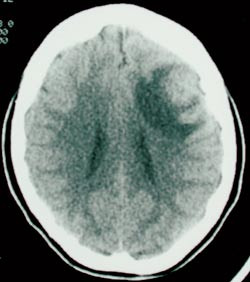

Laboratorieprøver viste Hb 9,5, hvite blodceller 7,6, CRP 29, SR 36. Elektrolytter, blodsukker, lever- og nyrefunksjonsprøver var normale. HIV-test negativ. CT caput (fig 1) viste 2 cm stor kontrastoppladende ringlesjon med ødem frontotemporalt på venstre side. Man mistenkte tumor, eventuelt abscess, og det ble startet behandling med antibiotika, fenytoin og deksametason.

11 dager etter innkomst ble det gjort kraniotomi. Det er beskrevet meget seig cortex, patologisk oppbløtt underliggende hvit substans og en relativt velavgrenset, seig og karfattig prosess. Denne ble fjernet. Frysesnitt viste kronisk betennelse med nekrose og granulomdanning. To dager postoperativt ble det påvist genmateriale fra Mycobacterium tuberculosis-komplekset ved PCR-undersøkelse, og man startet vanlig tuberkulosebehandling med fire medikamenter. Endelig histologidiagnose var nekrotiserende granulomatøs betennelse med kjempeceller. Det ble ikke påvist syrefaste staver ved mikroskopi, og dyrking for mykobakterier var negativ. Det videre forløpet var ukomplisert. Fenytoin ble seponert etter to år, og pasienten har ikke hatt flere krampeanfall.